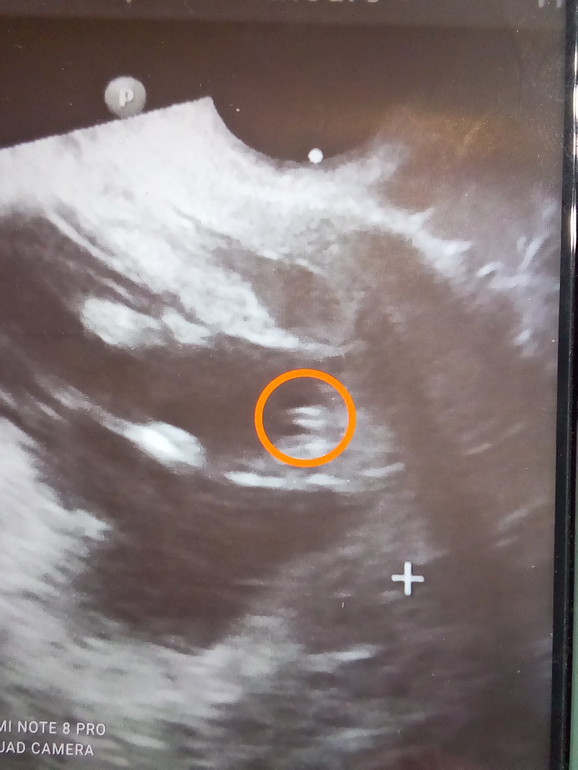

Но я всё таки надеюсь на мальчика, на фото с прошлого УЗИ я разглядела на половом бугорке линейное образование посередине, и

вот что я нашла:

В 12 недель можно разглядеть первые различия - у мальчиков на половом бугорке будет линейное образование посередине, а у девочек видно 4 параллельные линии. Линейное образование у мальчиков - это будущие мошонка и пенис, а 4 параллельные линии у девочек - это будущие половые губы.